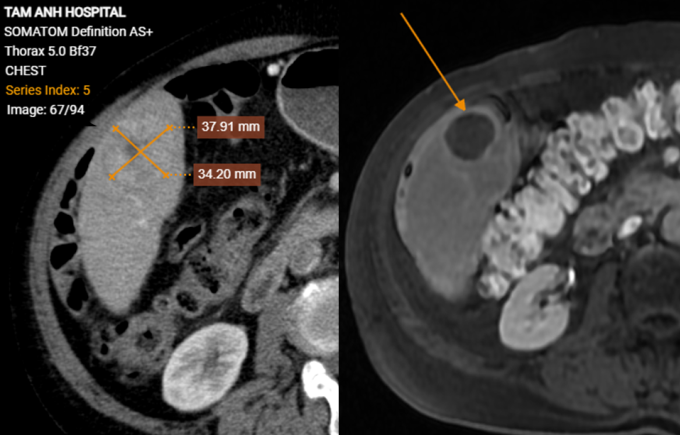

Ông Phong không có triệu chứng bất thường, siêu âm tầm soát ung thư gan do hút thuốc hơn 30 năm, tiền sử xơ gan, viêm gan siêu vi B, kết quả có khối giảm âm trong gan. Xét nghiệm máu ghi nhận mức AFP (chỉ điểm ung thư gan) trên 1440 ng/ml, gấp hơn 200 lần ngưỡng bình thường. Ảnh chụp CT phát hiện hai khối u gan kích thước 15x20 mm và 37x34 mm, bệnh nhân còn bị lóc tách động mạch chủ ngực, xơ vữa, phình, giãn một số động mạch chủ khác và hẹp 56% gốc động mạch thân tạng.

Tái khám sau ba tháng, kết quả chụp MRI ghi nhận hai khối u gan bệnh nhân giảm đáng kể kích thước, không còn ngấm thuốc, các tế bào ung thư đã hoại tử. Ông Phong có sức khỏe tổng thể tốt, tăng cân, chỉ số AFP giảm về ngưỡng bình thường 6,5 ng/ml, đáp ứng hoàn toàn với điều trị, theo bác sĩ Hiền.